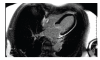

Takotsubo cardiomyopathy (TCM) is usually characterized by transient left ventricular apical ballooning. Due to the clinical symptoms which include chest pain, electrocardiographic changes, and elevated myocardial markers, Takotsubo cardiomyopathy is frequently mimicking ST-elevation myocardial infarction in the absence of a significant coronary artery disease. Otherwise an acute occlusion of the left anterior descending coronary artery can produce a typical Takotsubo contraction pattern. ST-elevation myocardial infarction (STEMI) is frequently associated with emotional stress, but to date no cases of STEMI triggering TCM have been reported. We describe a case of a female patient with inferior ST-elevation myocardial infarction complicated by TCM.